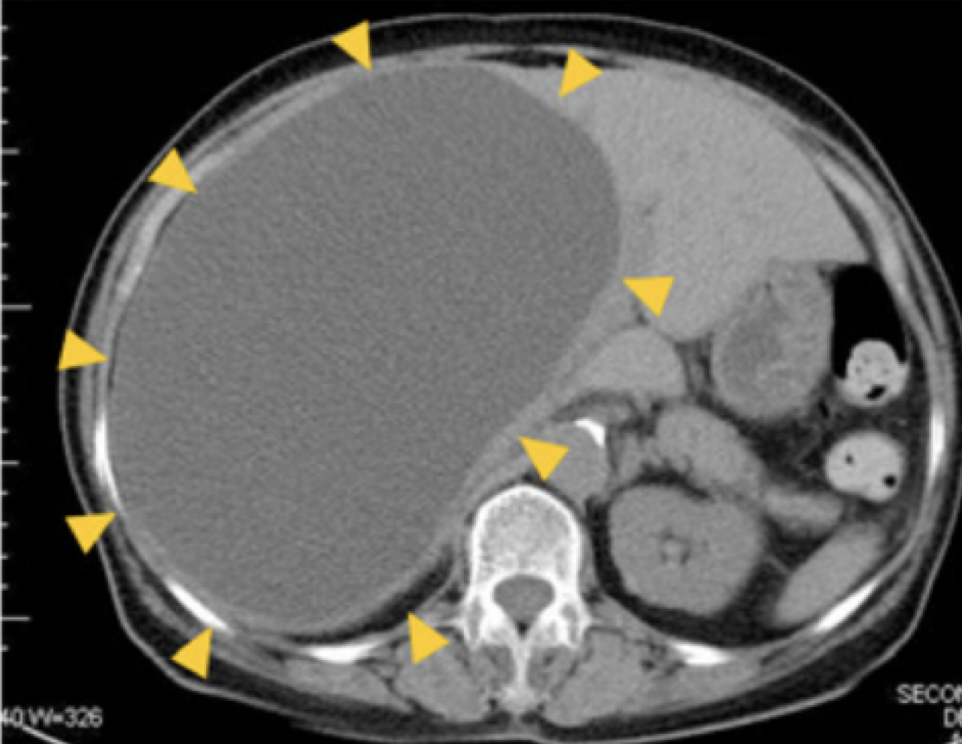

左図の ▲ に囲まれた部分が肝のう胞です。

これくらい大きくなるとおなかが張って苦しくなったり、違和感、満腹感などが出てきます。